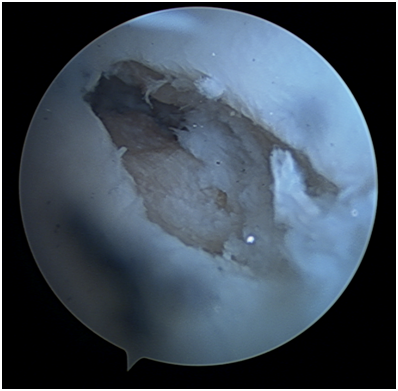

Case report on a 21-year-old patient with scaphoid neck pseudarthrosis with three years of evolution and with an MRI that does not reveal avascular necrosis of the proximal pole (Figures 1 & 2).

Figure 1 CT image showing pseudarthrosis of scaphoid waist.